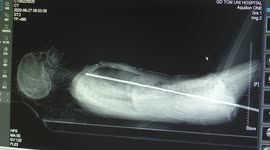

Chinese doctor removes pin from 7-month-old boy's body after he swallowed it

A doctor in southern China removed a pin from a 7-month-old boy’s body after he swallowed it.

The video, captured in the city of Chengdu in Sichuan Province on April 3, shows a doctor named Liu Yinghua using a tool to take a 2-centimetre-long pin out of a baby’s body during surgery.

According to reports, the baby mistakenly swallowed the pin when he was playing.

Fortunately, the pin was removed successfully and the baby has discharged from the hospital after two days of observation.